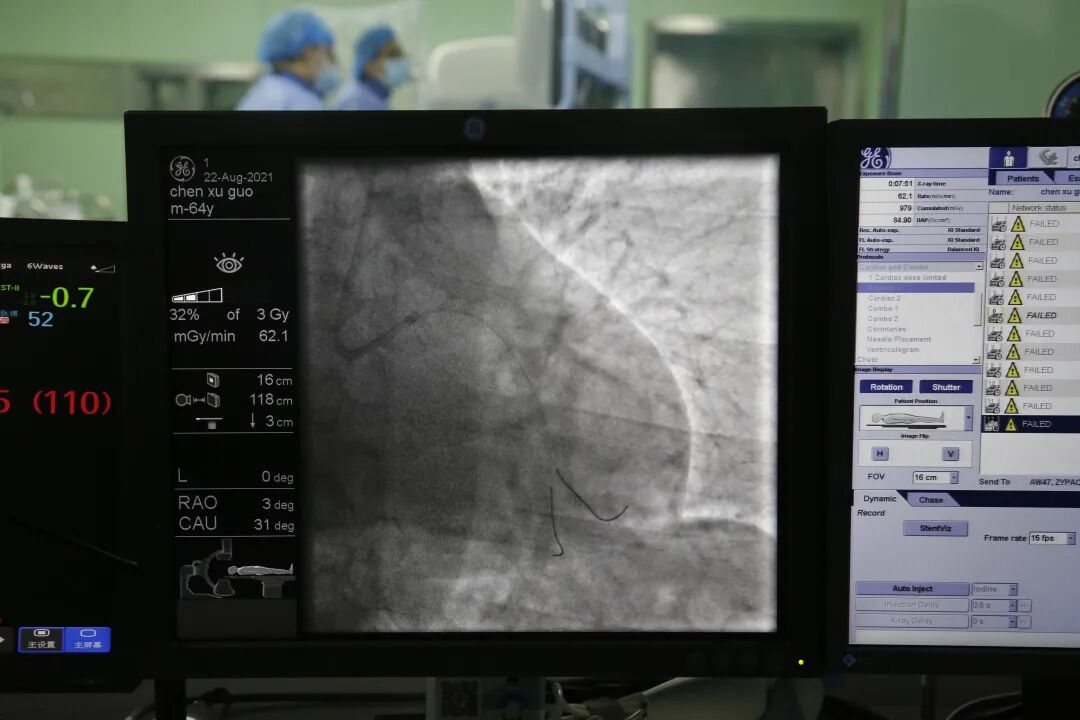

经与患者家属沟通,决定对病变明显的回旋支行PCI术,对其他病变血管暂时行内科药物保守治疗。术中应用导丝分别送至回旋支远端及钝缘支远端,应用球囊预扩张后造影显示病变血管狭窄改善不明显,遂给予支架一枚释放于回旋支中段至钝缘支开口,血管狭窄得到显著改善,手术顺利,病人术中无不适,拔除鞘管局部加压包扎,患者安返病房。